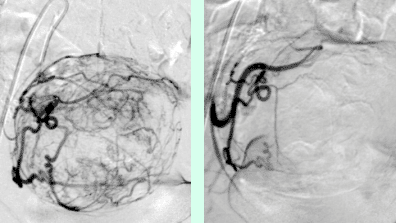

Abbildung 1: Übersichtsangiographie der Leber und superselektive Lage des Mikrokatheters vor Embolisation.

© Universitätsklinik für Radiologie und Nuklearmedizin

Abbildung 2: Angiographiekontrolle nach Embolisation. Die Tumor versorgenden Gefäße sind verschlossen.

Abbildung 3: Lebertumor vor und nach Embolisation.